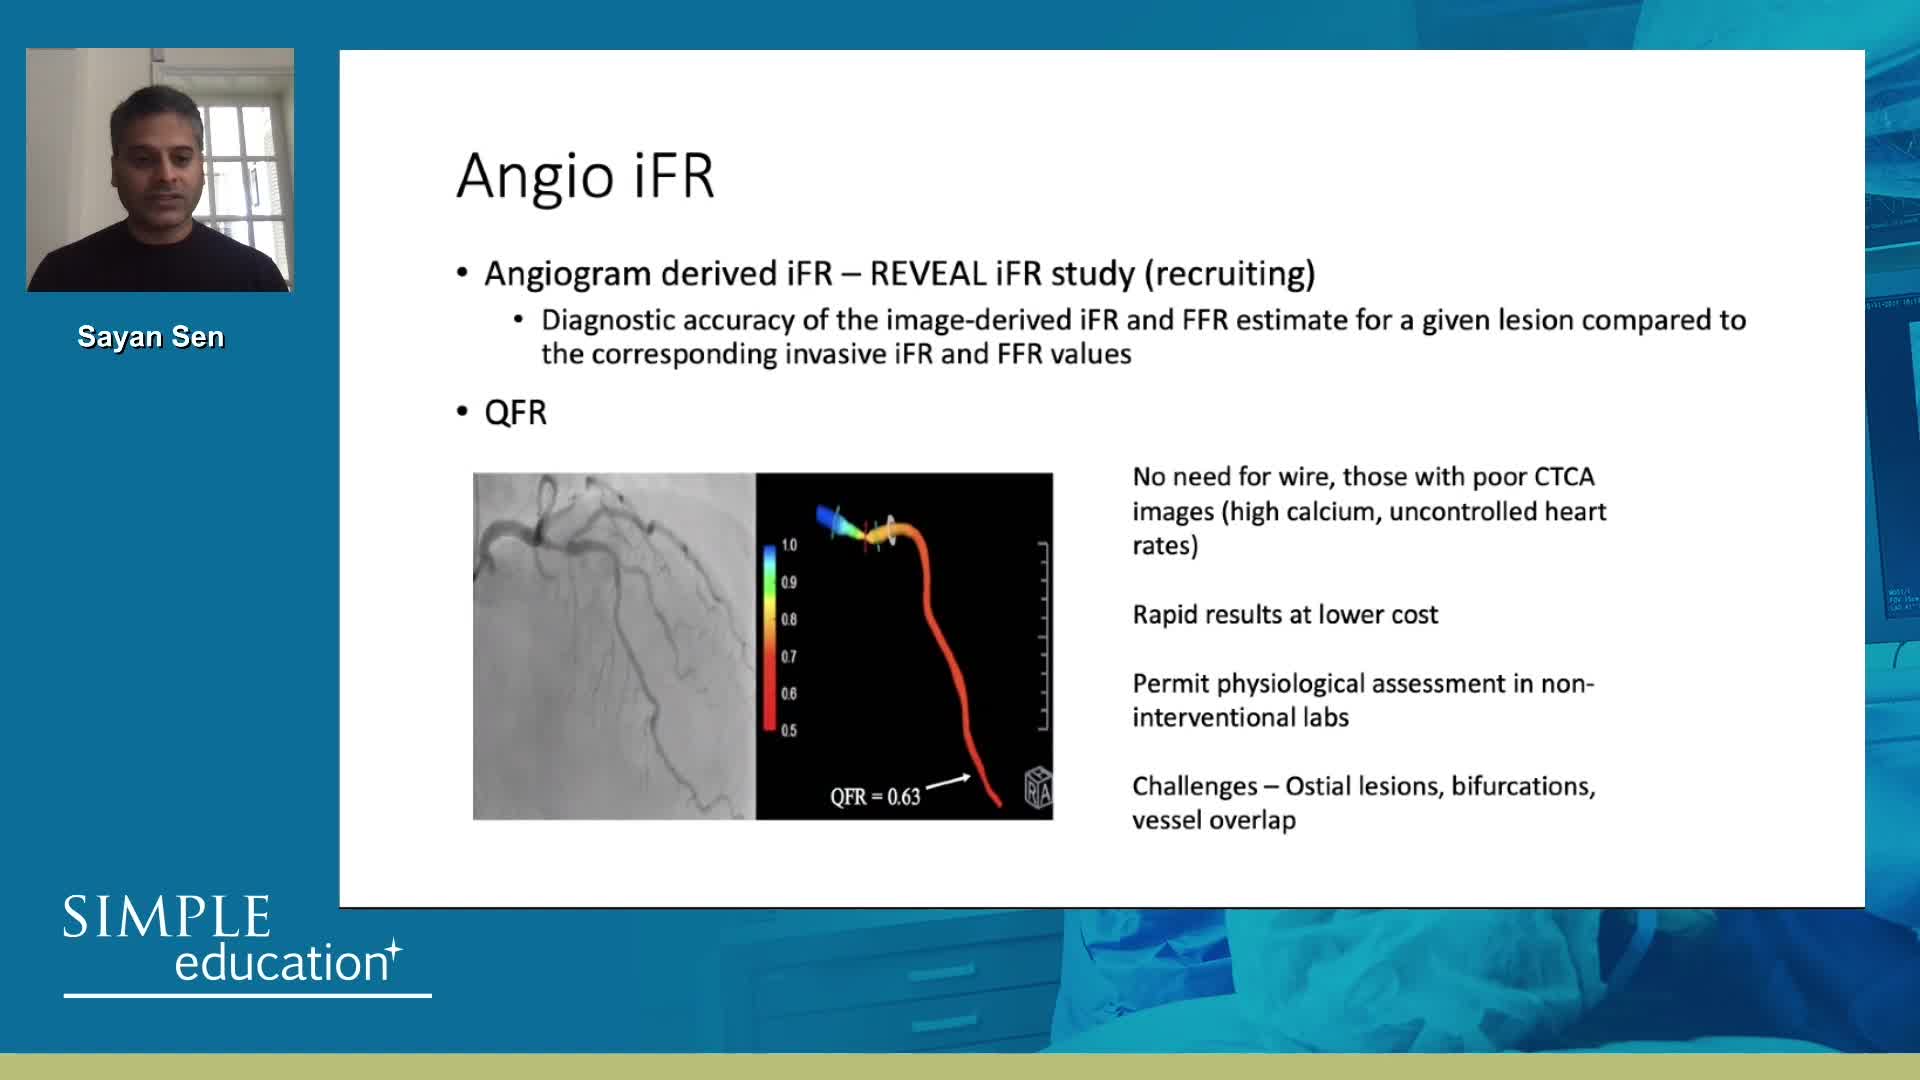

iFR or FFR in the LAD. What does the clinical outcome data tell us? - Dr Sayan Sen